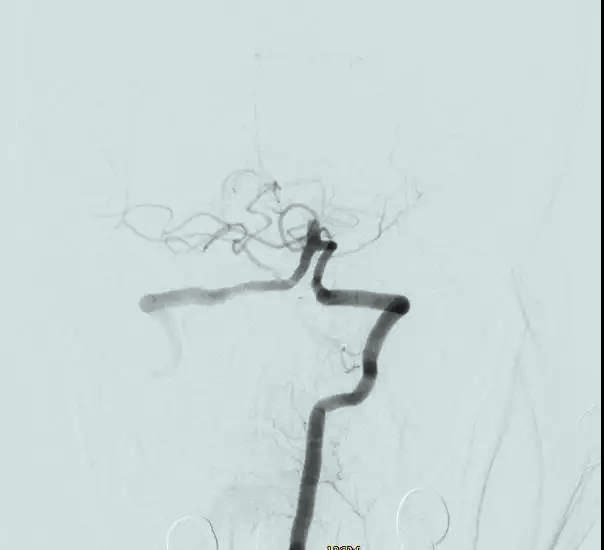

在神經(jīng)外科戴偉民主任的帶領下,李運平、劉榮財醫(yī)生默契配合,團隊協(xié)作為搶救生命爭分奪秒。“全麻及動脈置鞘,基底動脈起始部完全閉塞?!蹦X血管造影再次印證葉女士危在旦夕?!霸偻硪环昼?,后果不堪設想!” DSA導管室,一場與時間賽跑的生命爭奪戰(zhàn)正在進行。定點、介入,從放置取栓裝置到送達栓塞部位,每一個動作都“重若千鈞”,終于在3毫米的動脈導管內(nèi)完整取出5X3毫米的血栓,復查造影,顯示基底動脈血流恢復,取栓成功。而此時,距離葉女士抵達DSA導管室,僅僅過去了20分鐘。

取栓前

取栓后